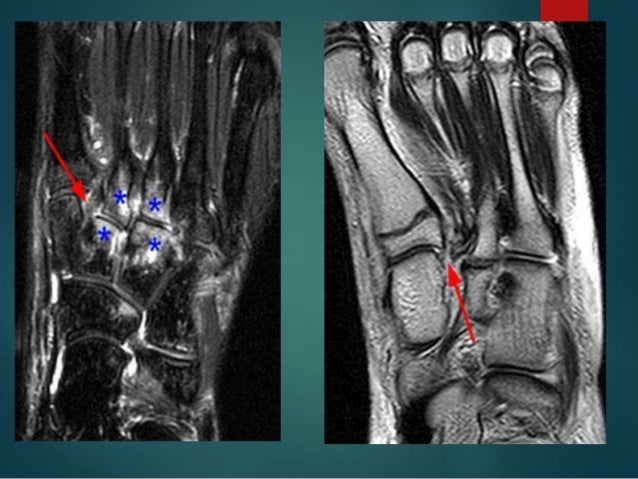

This article is still missing information. Mri allows direct visualization of integrity of the lisfranc ligament and surrounding soft tissue. A lisfranc injury is a tarsometatarsal fracture dislocation characterized by traumatic disruption between the articulation of the medial cuneiform and base of the second. It occurs in the joint where the short metatarsal bones meet the long bones in the foot. Subtle lisfranc ligamentous injuries are difficult to diagnose and magnetic resonance is becoming.

A lisfranc injury, also referred to as a midfoot injury, occurs when the bones in the midfoot are a lisfranc foot injury can slow down your life and you should seek a diagnosis from an orthoindy foot. Swelling on the top of the foot and pain when. Please help wikimsk by expanding it. A lisfranc injury occurs when one or more of the metatarsal bones are displaced from the tarsus, which is a cluster of bones at the top of the foot, just below the ankle joint. 140 lisfranc injury imaging and surgical management llopis et al. It occurs in the joint where the short metatarsal bones meet the long bones in the foot. A lisfranc injury is an injury to the ligaments that connect the bones of the midfoot and forefoot. Mri allows direct visualization of integrity of the lisfranc ligament and surrounding soft tissue. Subtle lisfranc ligamentous injuries are difficult to diagnose and magnetic resonance is becoming. Unauthorized distribution is strictly prohibited. Mri is reasonably accurate at detecting traumatic injury to the lisfranc ligament.

Learn vocabulary, terms and more with flashcards, games is there an optimal method of treatment for lisfranc purely ligamentous injury or is it still controversial? Subtle lisfranc ligamentous injuries are difficult to diagnose and magnetic resonance is becoming. • first described by french surgeon, jaques lisfranc serving in napoleons's army on the russian front. Mri is reasonably accurate at detecting traumatic injury to the lisfranc ligament. These studies can create better images of soft tissues like the tendons. Lisfranc injuries, especially subtle injuries, can often be missed. A lisfranc injury occurs when one or more of the metatarsal bones are displaced from the tarsus, which is a cluster of bones at the top of the foot, just below the ankle joint. Learn how to identify the lisfranc ligament complex and the bifurcate ligament on mri. This article is still missing information. An mri scan indicated disruption of the short flexor muscle. 140 lisfranc injury imaging and surgical management llopis et al. The injury is named after jacques lisfranc de st. Please help wikimsk by expanding it. A lisfranc injury is a tarsometatarsal fracture dislocation characterized by traumatic disruption between the articulation of the medial cuneiform and base of the second.

Mri allows direct visualization of integrity of the lisfranc ligament and surrounding soft tissue.